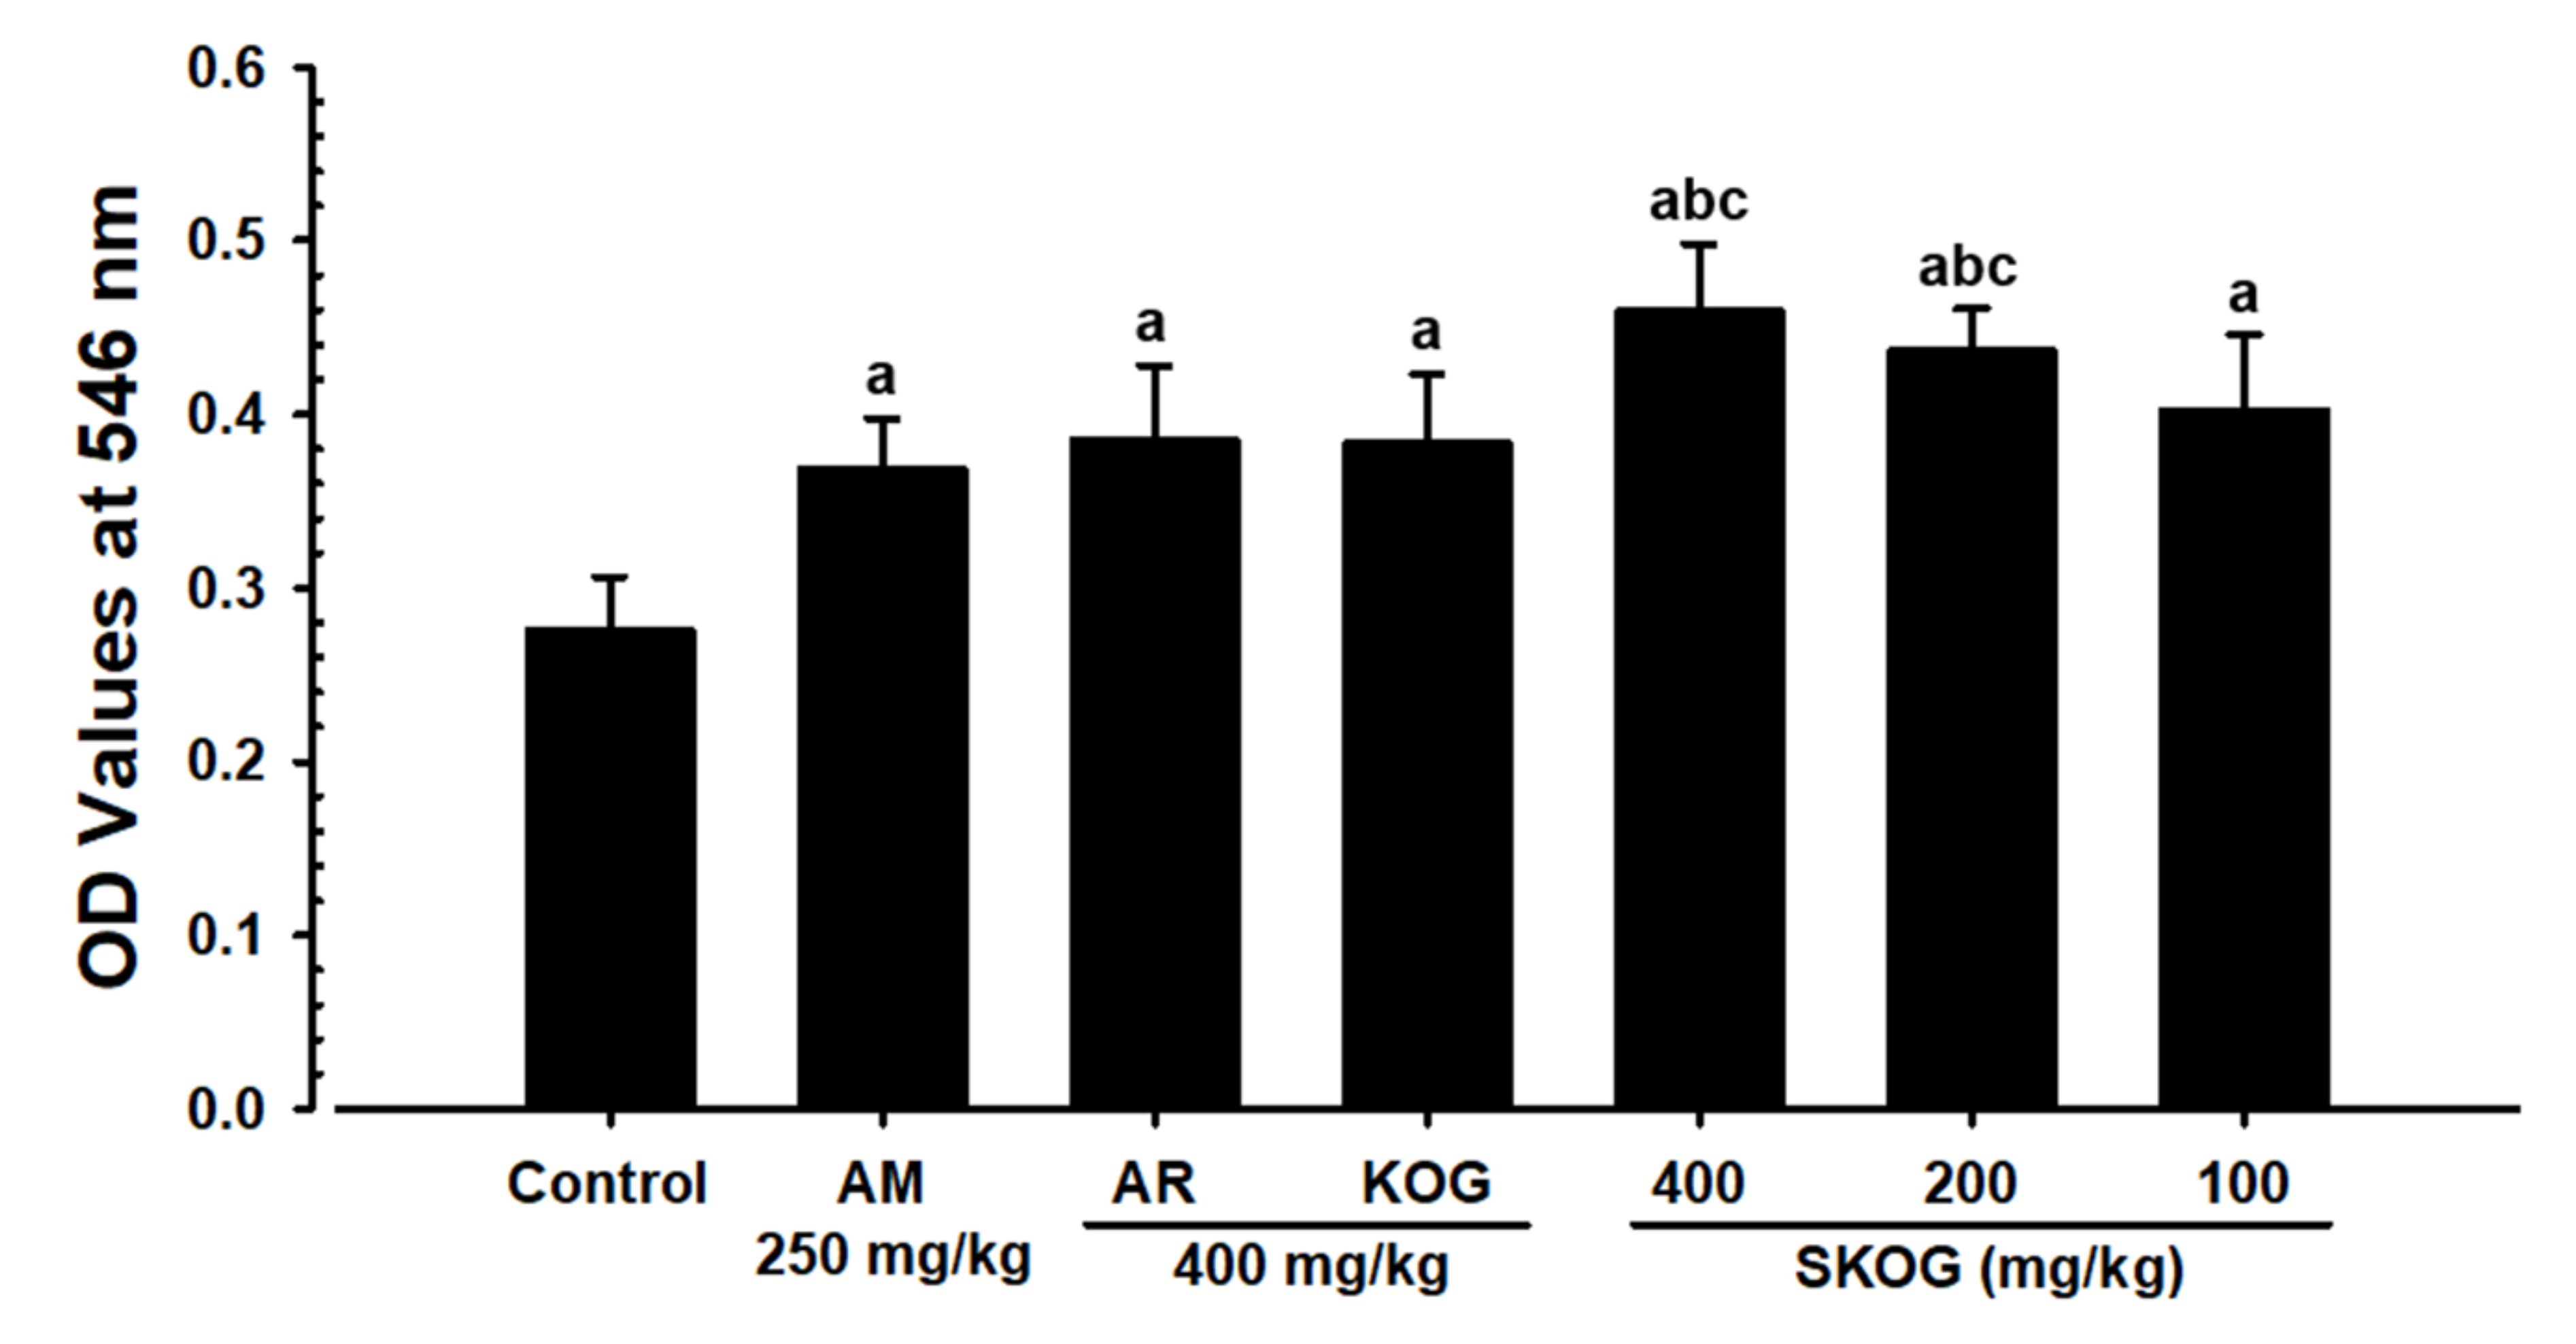

3.3.3. Changes in Mucous Secretion

3.3.4. Histopathological Findings in the Intrapulmonary Secondary Bronchus